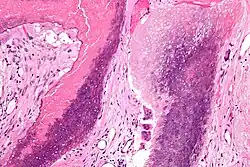

Histopathology of pilomatricoma, high magnification, H&E stain, showing the characteristic components of basaloid cells and ghost cells. | |

The characteristic components of a pilomatricoma include a stroma of fibrovascular connective tissue surrounding irregularly shaped, lobulated islands containing basaloid cells (being darkly stained, round or elongated, with indistinct cell borders and minimal cytoplasm, with nuclei being round to ovoid, deeply basophilic and generally prominent nucleoli), which abruptly or gradually transitions into ghost cells (having abundant, pale, eosinophilic cytoplasm, well defined cell borders and a central clear area, but only faint traces of nuclear material), which in turn may transition into keratinaceous to amorphous necrosis.[11]

The presence of calcifications with foreign-body giant cells is common within the tumors.[12]